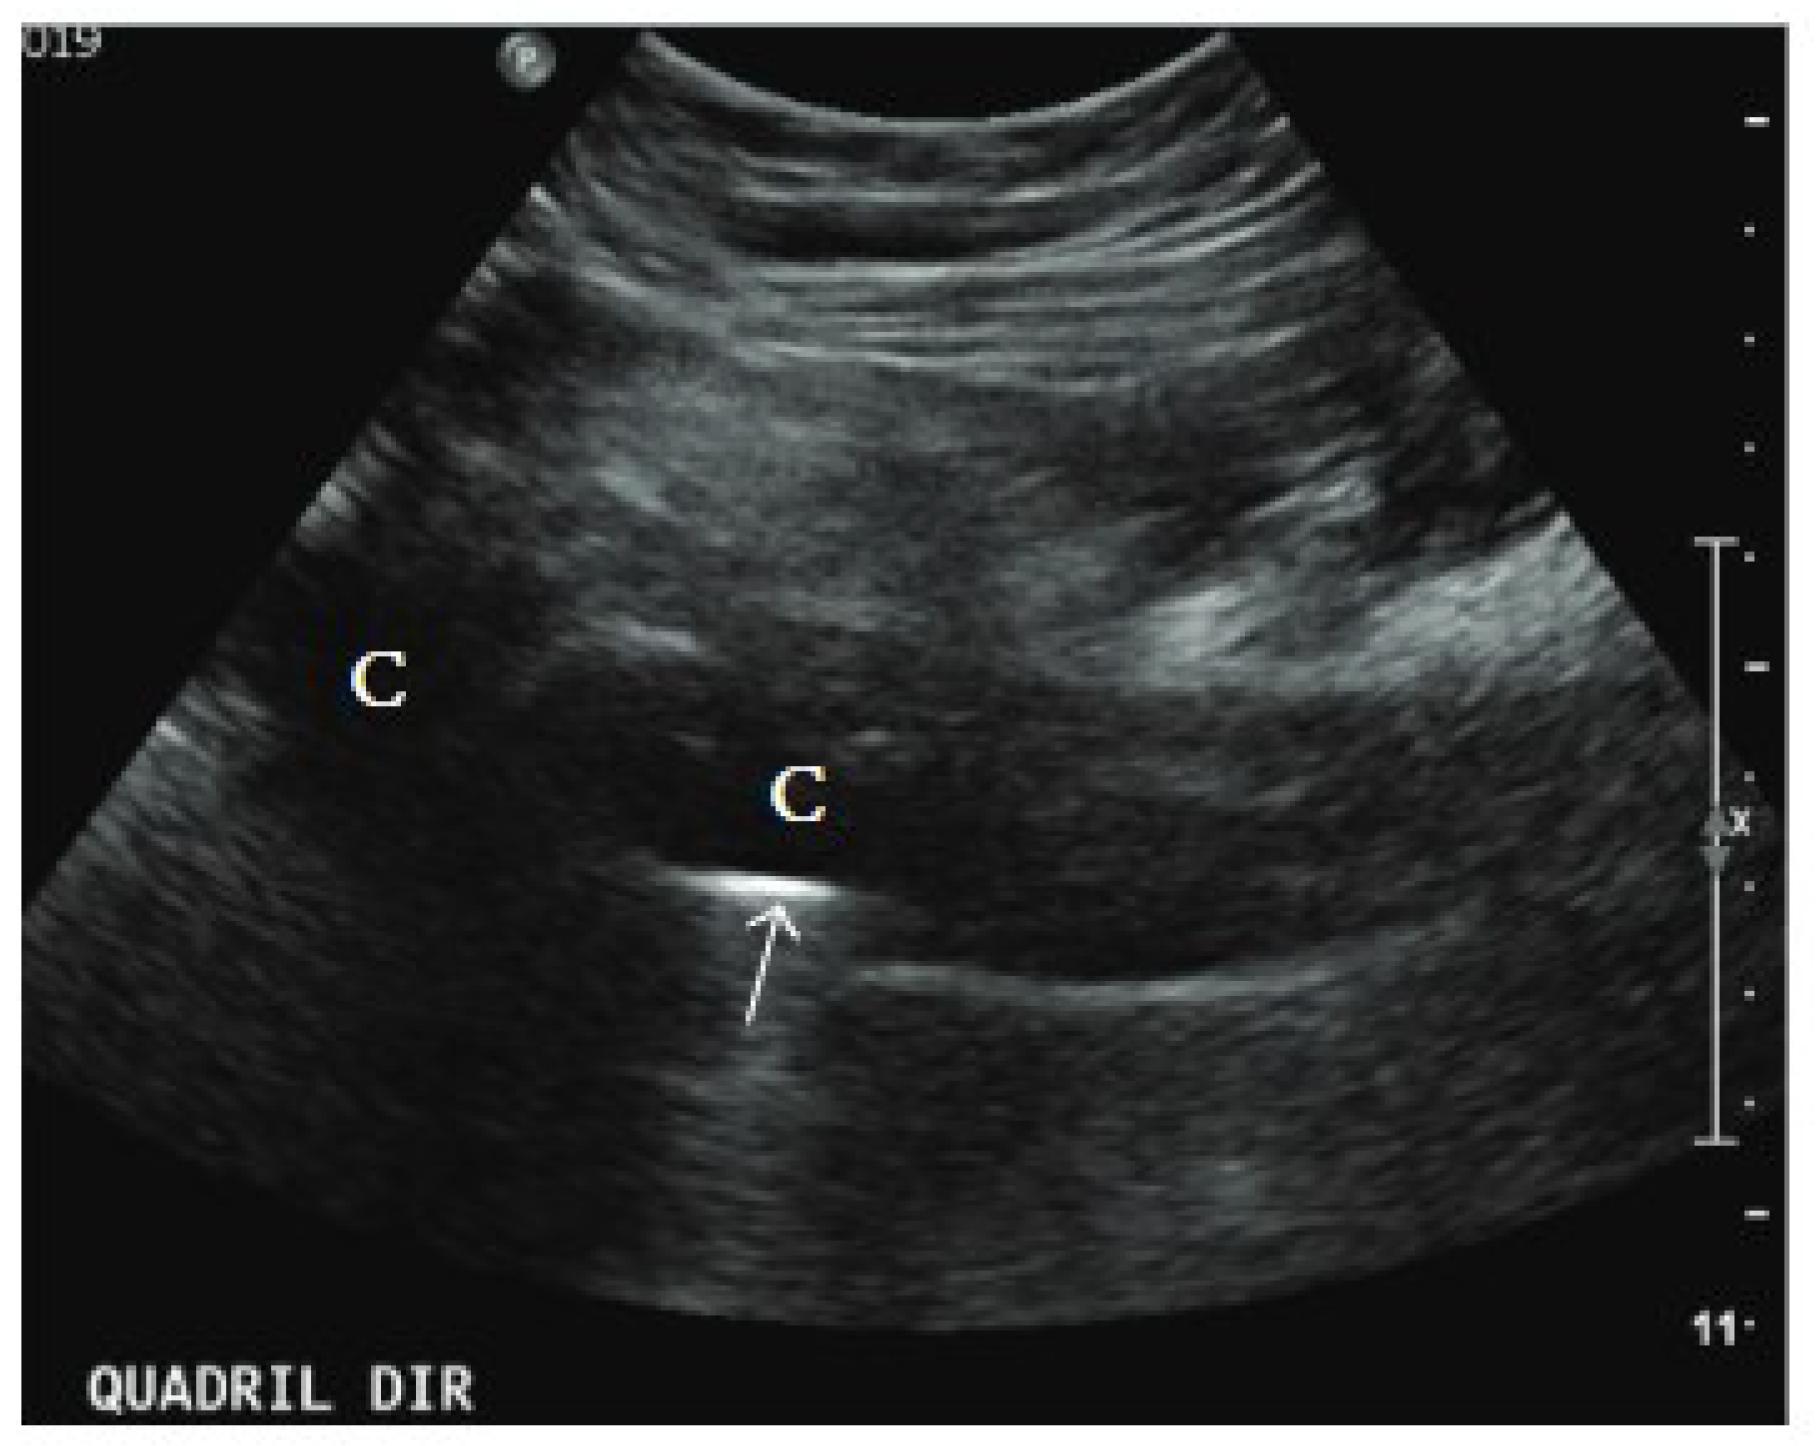

4.2. Ultrasound

- Bureau, N.J.; Ali, S.S.; Chhem, R.K.; Cardinal, E. Ultrasound of musculoskeletal infections. In Seminars in Musculoskeletal Radiology; Thieme Medical Publishers: New York, NY, USA, 1998; pp. 299–306. [Google Scholar]

- Soliman, S.B.; Davis, J.J.; Muh, S.J.; Vohra, S.T.; Patel, A.; van Holsbeeck, M.T. Ultrasound evaluations and guided procedures of the painful joint arthroplasty. Skelet. Radiol. 2022, 51, 2105–2120. [Google Scholar] [CrossRef]

- Craig, J.G. Ultrasound of the postoperative hip. In Seminars in Musculoskeletal Radiology; Thieme Medical Publishers: New York, NY, USA, 2013; pp. 49–55. [Google Scholar]

- Nyamankolly, E.; Leitao, J.; Lescure, M.; Shipley, E.; Mazé, J.; Desclaux, A.; Dutronc, H.; Neau, D.; Dauchy, F.-A. Ultrasonography performed by an infectiologist in hip and knee prosthetic joint and native joint infections. Infect. Dis. Now. 2023, 53, 104689. [Google Scholar] [CrossRef]

- Wei, W.; Huang, X.; Huang, L.; Xie, L.; Li, W.; Gong, Y.; Chen, S. Application of Ultrasound in Diagnosis of Prosthesis Loosening and Infection After Total Hip Arthroplasty. Res. Sq. 2021; preprint. [Google Scholar]

- Abbas, H.M.; Maged, A.M.; Elshewi, E. Role of Ultrasonography in Prosthetic Joint Infection Diagnosis and Assessment. Med. J. Cairo Univ. 2022, 90, 1633–1642. [Google Scholar] [CrossRef]

- Battaglia, M.; Vannini, F.; Guaraldi, F.; Rossi, G.; Biondi, F.; Sudanese, A. Validity of preoperative ultrasound-guided aspiration in the revision of hip prosthesis. Ultrasound Med. Biol. 2011, 37, 1977–1983. [Google Scholar] [CrossRef]

- Eisler, T.; Svensson, O.; Engström, C.-F.; Reinholt, F.; Lundberg, C.; Wejkner, B.; Schmalholz, A.; Elmstedt, E. Ultrasound for diagnosis of infection in revision total hip arthroplasty. J. Arthroplast. 2001, 16, 1010–1017. [Google Scholar] [CrossRef]

- Bengtzen, R.R.; Lee, J. Point-of-Care ultrasound and the septic prosthetic hip joint. J. Emerg. Med. 2019, 57, 701–704. [Google Scholar] [CrossRef] [PubMed]